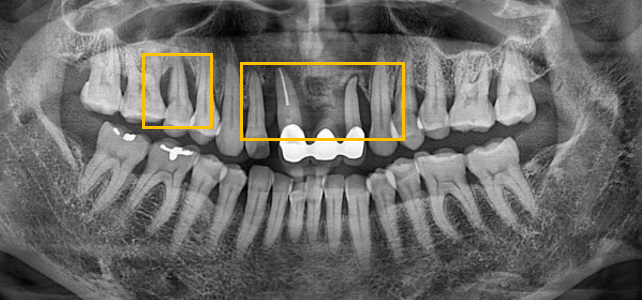

임플란트 치료를 진행 하려고 하는 부분들을 파노라마 상으로 보게 되면

잇몸뼈들이 다 녹아 패여 있는 모습들을 볼 수 있는데요 뼈이식과 함께 진행 하였습니다.

임플란트가 제대로 식립되려고 하면 치아를 제대로 지지하는 잇몸뼈처럼

임플란트도 제대로 지지 가능한 잇몸뼈가 필요합니다.

뼈이식 이후 잇몸뼈가 제대로 결합될때까지 길게는 6개월 이상 보통은 2~3개월 소요됩니다.

이 환자분은 상악의 임플란트 뼈이식 이후 최종 보철까지는 4개월 정도 소요 되었습니다.